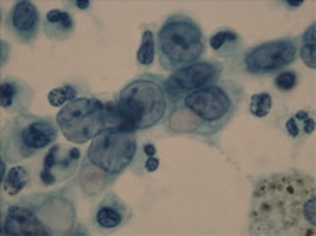

細胞診は、はがれてきた(喀痰細胞診)あるいは剥がしてきた(擦過細胞診)もしくは針を刺して吸引してきた(吸引細胞診)細胞をアルコール固定し、パパニコロー染色という方法で染めて顕微鏡で見ます。細胞の並び方を判断することは困難で、主として細胞の大きさ、形から判断します。

痰に混じったがん細胞を見つけ出す:喀痰細胞診

喀痰細胞診

喀痰とは吐き出した痰のことです。肺の組織から剥がれ落ちて痰に混じったがん細胞を検出する検査です。人間の目で喀痰中のがん細胞の有無をチェックします。検査は専門のスクリーナーという技師が行います。

検査の手順は、できるだけ早朝の喀痰を容器に入れ、乾かないようにして提出するだけです。患者さんにとって苦痛のない簡単な検査ですが、肺がんがあれば必ず痰にがん細胞が混じっているとは限らず、喀痰細胞診の結果が正常であったからといって肺がんがないという証拠にはなりません。

そのため喀痰細胞診は何回か繰り返し行うことで、がんがあった場合の診断精度が高まるとされており、通常3回は行って喀痰中のがん細胞の有無を調べることになっています。

医療施設から遠方にお住まいの人、忙しい人などに自宅で3日間痰をためてもらう方法もありますが、どうしても細胞が変性してしまうため、少し見にくい標本になってしまうようです。

細胞診検査では、検体(この場合痰のことです)をスライドグラスの上で伸ばしてアルコールで固定し、染色して顕微鏡で細胞を観察します。がん細胞があると疑われる場合には、スクリーナーとは別に医師が確認するという手順を踏みますので、結果が出るまでは数日かかります。